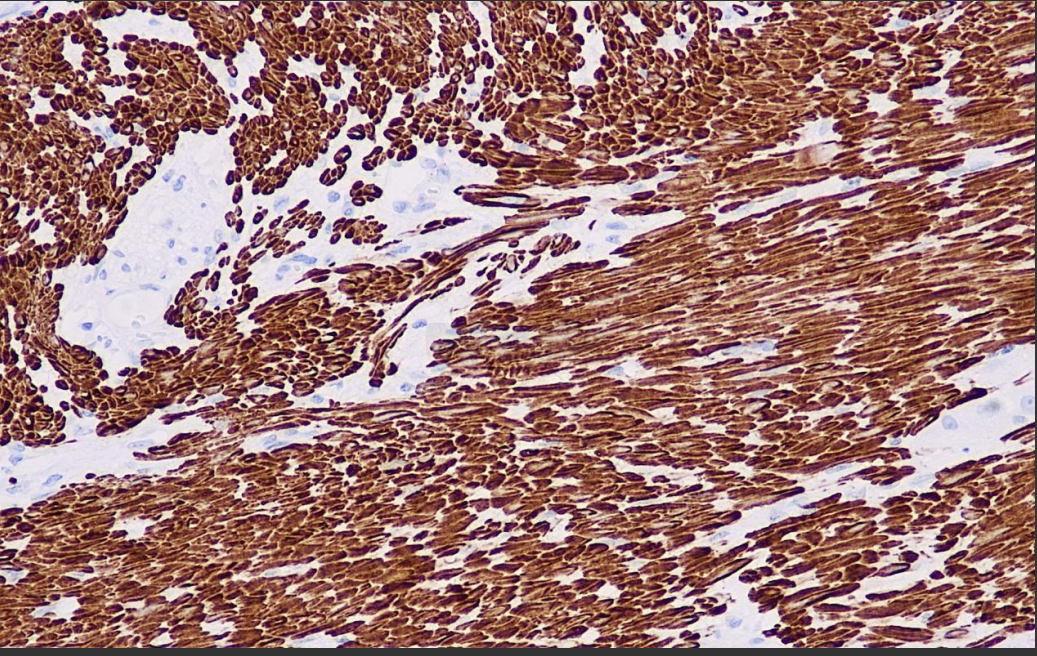

Calcium-binding protein is a smooth muscle actin and calmodulin binding protein located in fine myofilaments that regulates the interaction of actin and myosin and is a marker for smooth muscle cells. In colorectal tumors this antibody is a meaningful marker for distinguishing fibroblasts from myofibroblasts.

Caldesmon Antibody Reagent binds specifically to Caldesmon molecular antigen. Immunohistochemistry kits containing Caldesmon Antibody Reagent are indicated for the precise diagnosis of tumors of smooth muscle origin (e.g., smooth muscle tumors, smooth muscle sarcomas) and myofibroblastic lesions.